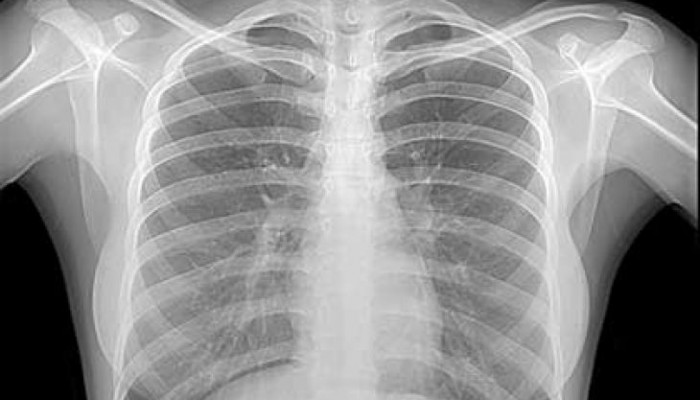

Что показывает рентген грудной клетки? При первом же взгляде внимание сразу задерживается на очертаниях скелета, которые выделяются на фоне тёмной лёгочной ткани. Кости хорошо задерживают излучение, поэтому на снимке они видны в форме ровных и светлых полос. Их состояние оценивается в следующем порядке:

- Сначала определяется симметричность снимка – для этого необходимо посмотреть в его верхнюю часть. Там располагаются ключицы, которые должны находиться горизонтально на одном уровне.

- Далее, оценивается положение лопаток – их при подготовке нужно было развести, чтобы их плотность не мешала описывать состояние лёгких. При нормальном положении они находятся по боковым краям снимка, как светлые треугольники. Их симметричность также важна для диагностики – внутренний и верхний края должны быть на одном уровне.

- Затем переходят к осмотру позвоночника – правильная техника выполнения позволяет увидеть лишь от 4 до 5 верхних грудных позвонков. Если их определяется больше, то для описания внутренних органов такой снимок не подходит.

- Последние начинают оцениваться рёбра – также описывается их симметричность, непрерывность, а также ширина межрёберных промежутков. Недостаточно глубокий вдох не позволит грудной клетке расправиться, что сразу же будет заметно по близкому положению этих костей.

Оценка состояния костей чаще встречается в практике травматолога, что позволяет диагностировать переломы костей грудной клетки и другие повреждения.